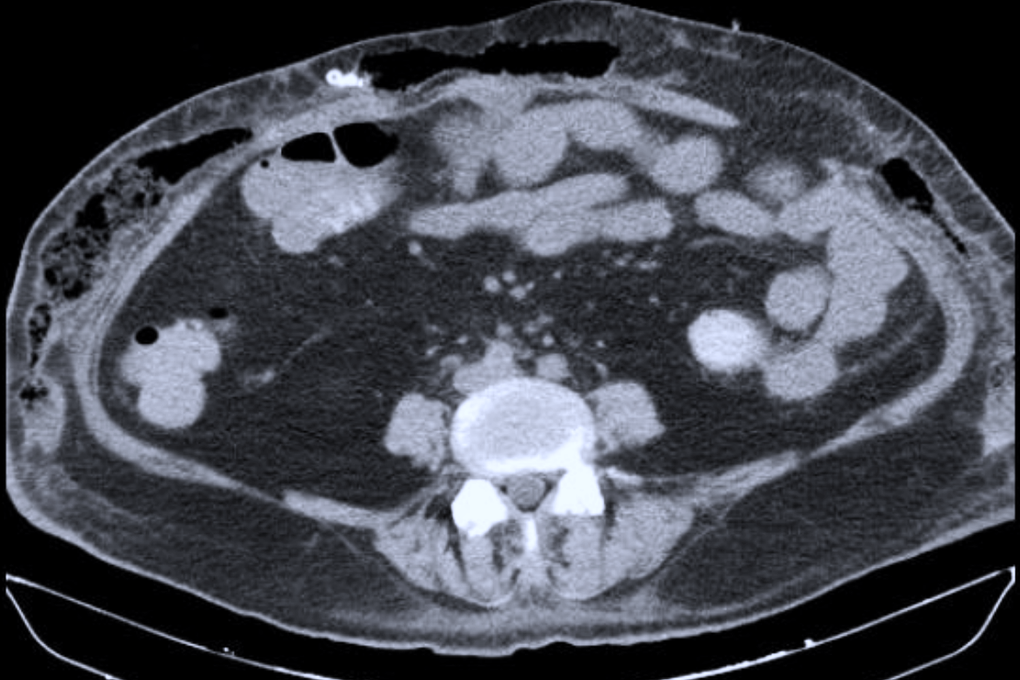

Khi vào Bệnh viện Quân y 175, bệnh nhân trong tình trạng suy hô hấp, sốc nhiễm khuẩn, tổn thương đa cơ quan, da vùng bụng phù nề lớn, có các điểm biến đổi màu sắc và đau nhiều. Ảnh chụp CT ổ bụng cho thấy có tụ dịch, tràn khí dưới da phần mềm thành bụng 2 bên và thoát vị thành bụng.

Hình ảnh CT ổ bụng của bệnh nhân (Ảnh: Bác sĩ cung cấp.